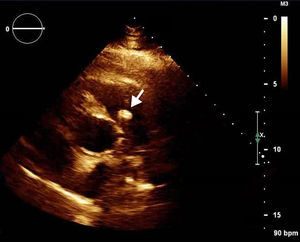

A 42-year-old man with a history of hypertension, type 2 diabetes mellitus and obesity was referred to our center due to the incidental finding of a mass adjacent to the pulmonary valve on a routine transthoracic echocardiogram (Figure 1). He was asymptomatic and physical examination and laboratory values were unremarkable. The transesophageal echocardiogram (Figure 2) revealed a pedunculated, highly mobile hyperechogenic mass, measuring 8 mm × 7 mm, attached to the right pulmonary valve leaflet. The pulmonary valve was functionally normal, with no observed pulmonary regurgitation or stenosis, and no masses were visualized on any other valves or heart chambers. Computed tomography angiography excluded significant coronary stenosis and confirmed the presence of a mass at the level of the pulmonary valve (Figure 3). We concluded that it most likely represented a papillary fibroelastoma. Surgical excision of the mass was decided upon due to its mobility and location, resulting in high risk for embolization. It was successfully resected, with preservation of the valve apparatus. Histopathological examination confirmed the diagnosis of papillary fibroelastoma (Figure 4).